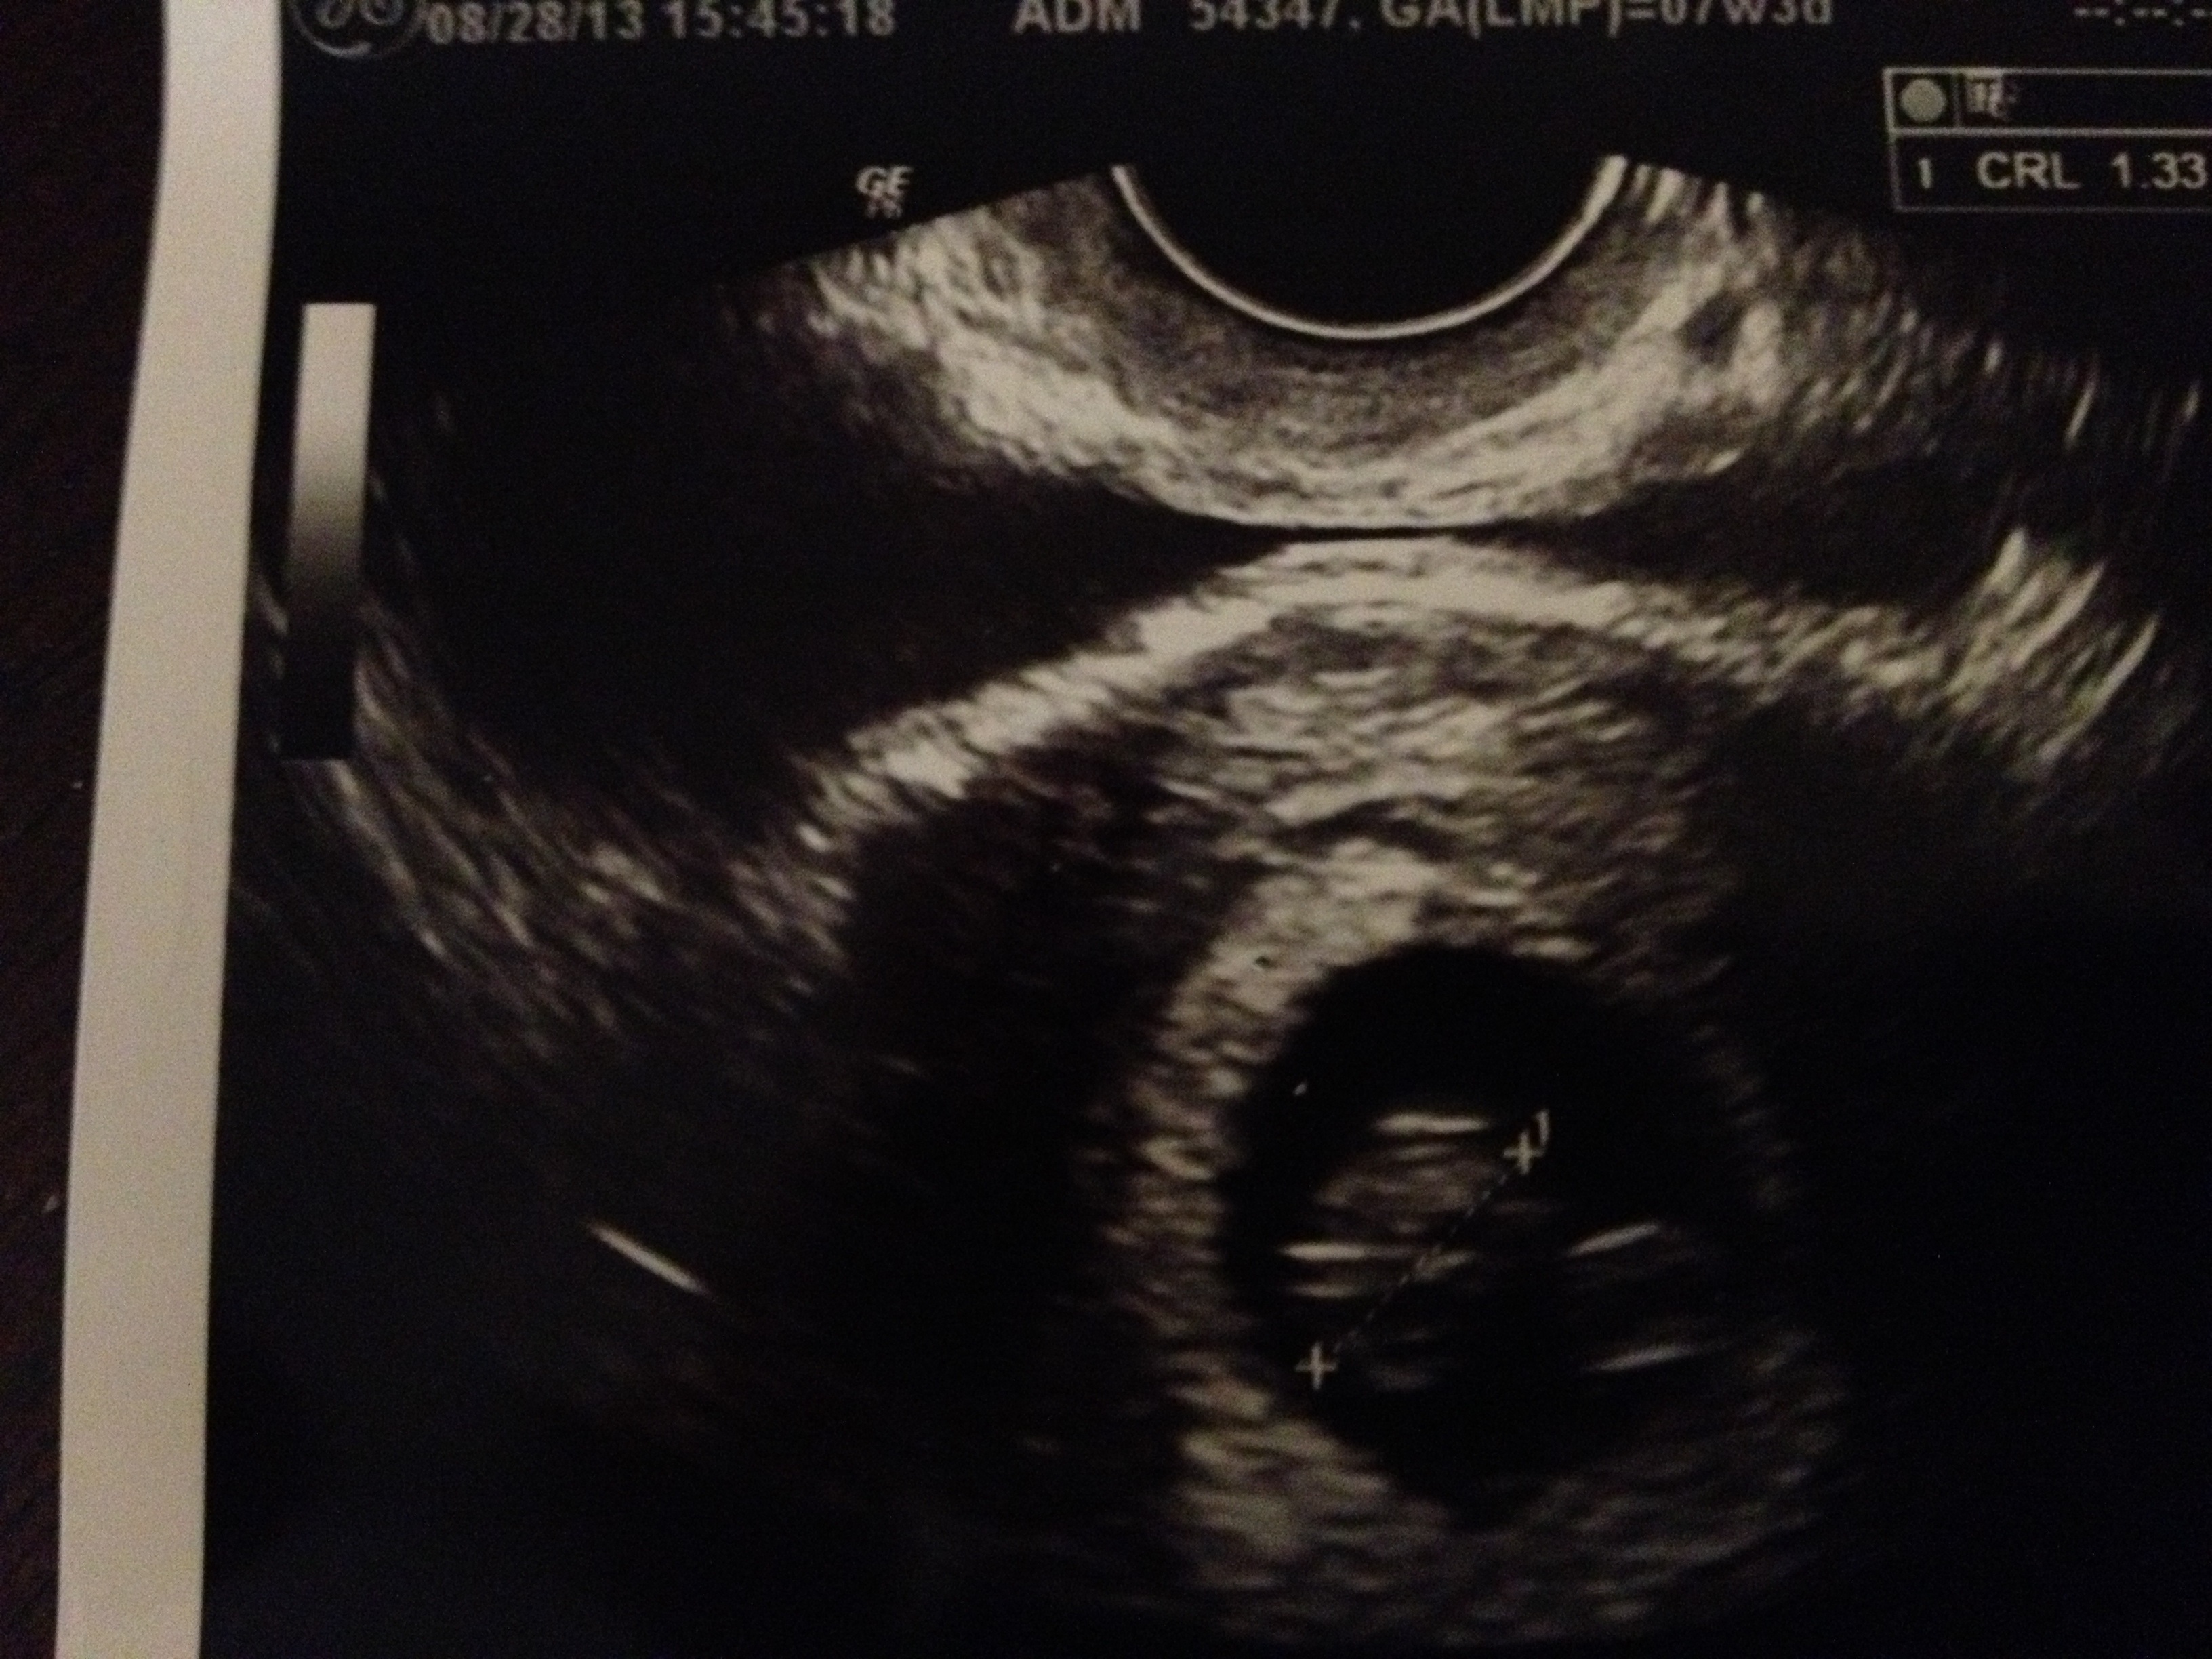

So had my first appt today and things are looking really great! Measuring 8w on the nose (ill update my ticker later) and heartbeat strong at 170! Posting from my phone so I hope the pics turn out ok.